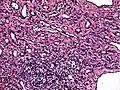

Low power photomicrograph of an endovascular papillary angioendothelioma showing papillae with hyalinized cores -

High power view showing a vascular tumor with cuboidal endothelium lining the vessels. Few entrapped seminiferous tubules are also noted (arrow). -

Characteristic budding, hobnail-like endothelial cells visible.